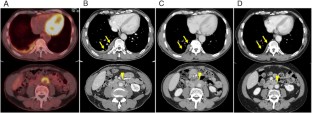

IgG4-related disease (IgG4-RD) is a fibro-inflammatory condition characterized by increased serum IgG4 level, infiltration of lymphocytes and IgG4-positive (IgG4+) plasma cells and fibrosis. It can occur in almost all organs, commonly affecting the pancreas, biliary tract, salivary and lacrimal glands and kidneys. However, reports of IgG4-RD accompanied by pathologically confirmed, IgG4-related pleural disease are scarce. Here, we present a case of a 64-year-old man with suspected malignant pleural mesothelioma based on imaging findings but finally diagnosed with IgG4-RD (including pleuritis, periaortitis and bilateral submandibular gland enlargement) based on a high serum IgG4 level and pleural histopathological findings such as lymphoplasmacytic infiltration including IgG4+ plasma cells and fibrosis. Systemic corticosteroid therapy was effective at reducing serum IgG4, improving bilateral submandibular gland enlargement, and regressing pleural thickening and periaortic soft tissue. We also discuss clinical characteristics and pleural pathological features of previously reported cases with IgG4-related pleural disease based on a comprehensive literature review. Our case of IgG4-RD with pleura, aorta and submandibular gland involvement, pathologically confirmed by pleural specimen might be unique and very rare.